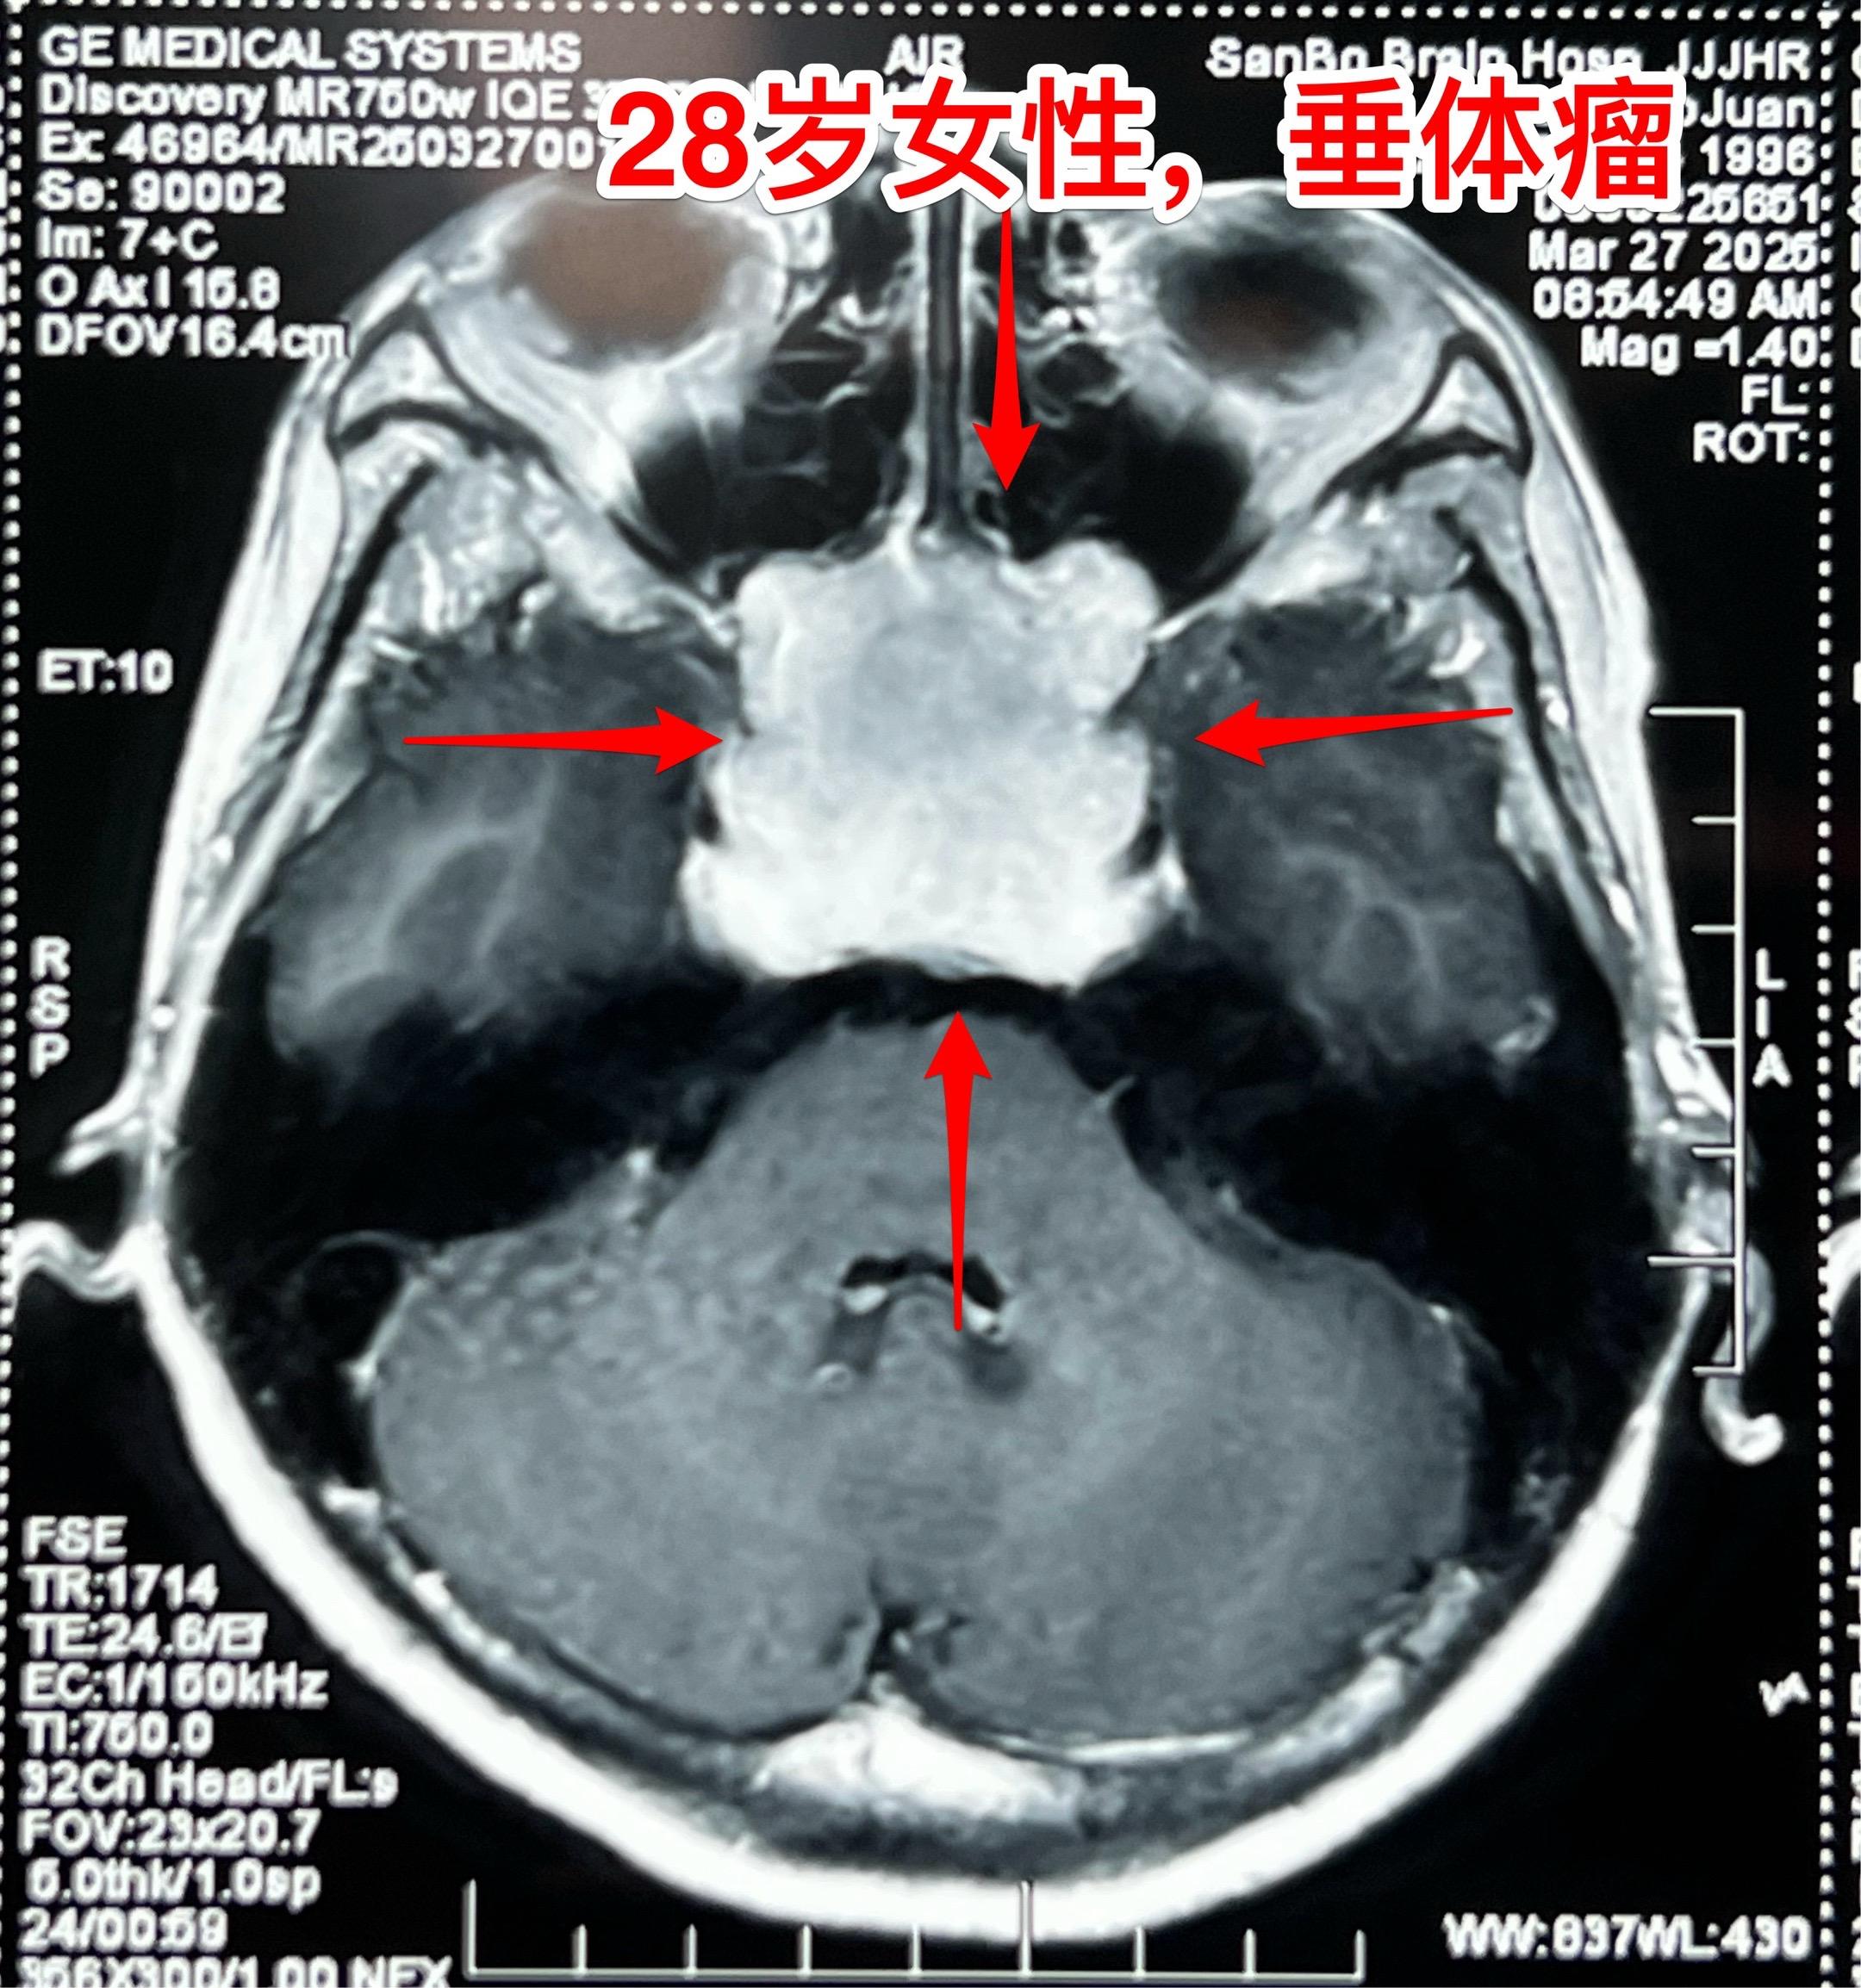

28岁女性6年前生完孩子就一直内分泌紊乱。山西省晋城市28岁女性,6年前生完孩子就一直没有生理周期,而且渐渐出现身体消瘦,视力下降。 作磁共振和CT发现脑部有一个巨大肿瘤,肿瘤周边似乎有钙化,见图3,怀疑为颅咽管瘤,就到北京三博脑科医院找我看病。 其实这个肿瘤是垂体瘤,肿瘤呈“顶天立地”状。化验激素显示TSH、T3、T4均高于正常,也就是说有甲亢。这是罕见的分泌TSH的垂体腺瘤。病人体重才80多斤! 今天是周日,加班为她作了手术。